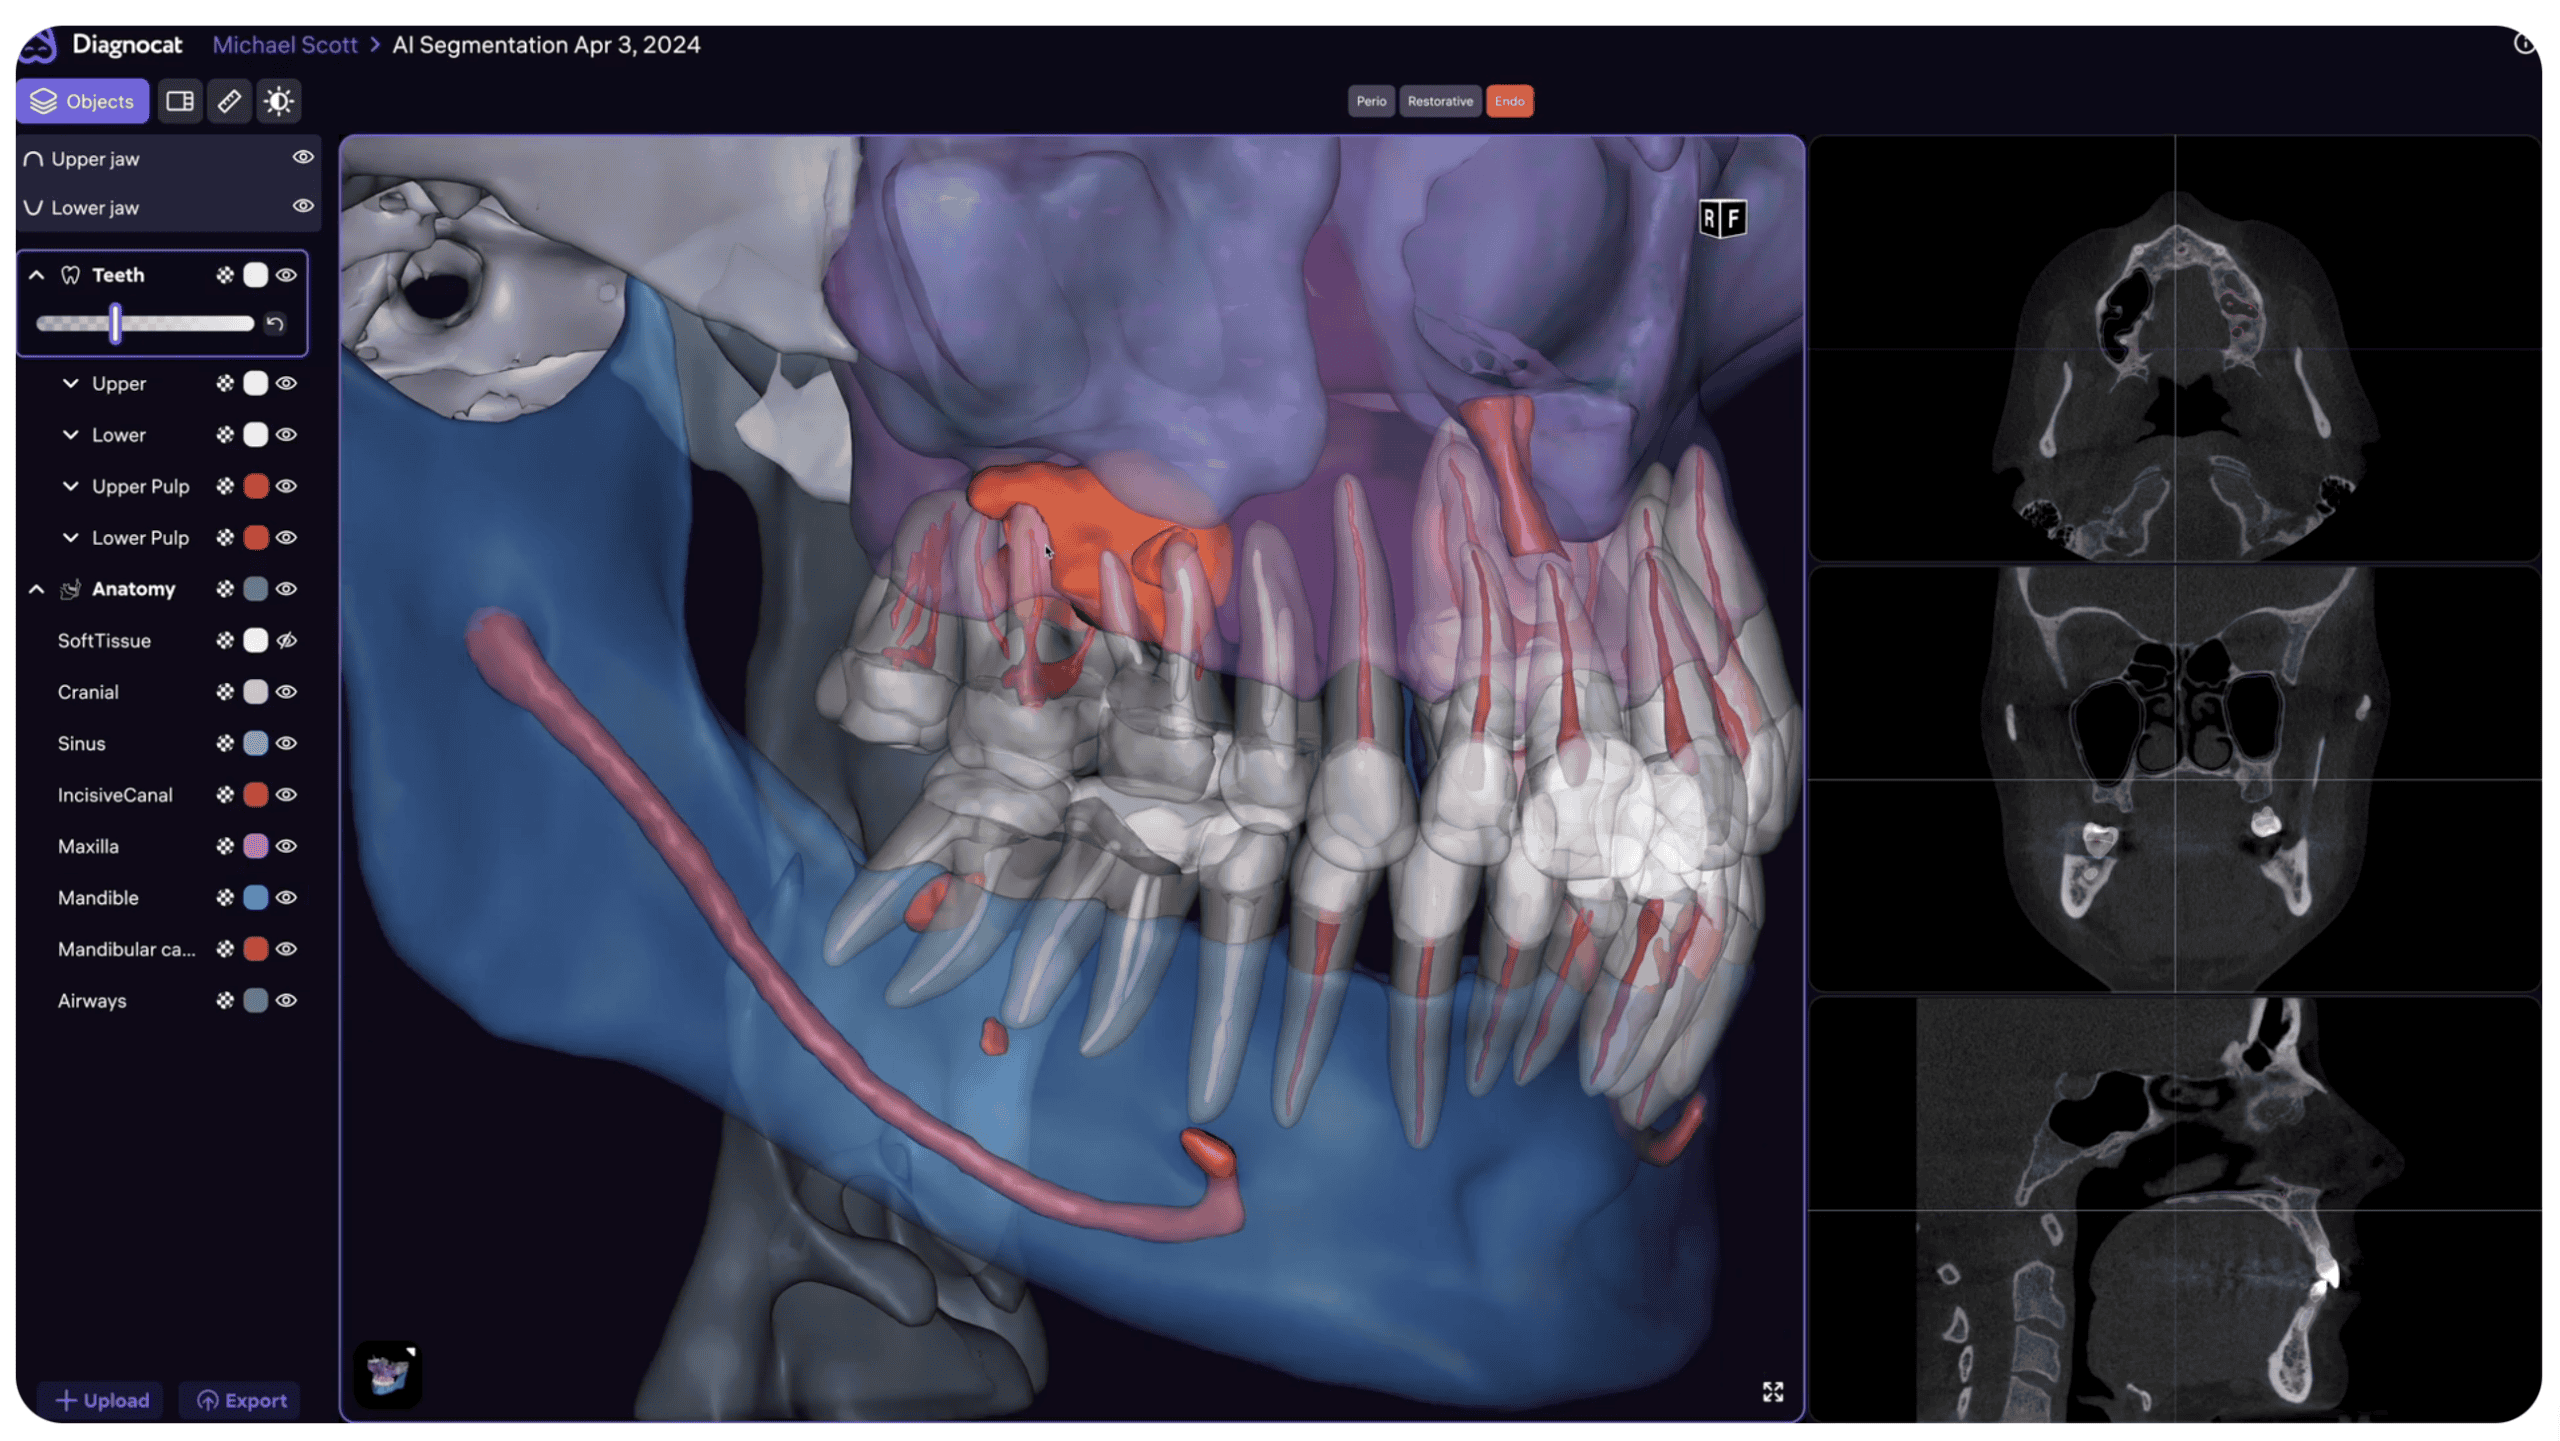

Cu ajutorul segmentării automate, CBCT-urile sunt reconstruite în modele 3D STL, ideale pentru consultații și o vizualizare clară a stării de sănătate orală. Aceste modele 3D sunt de neprețuit pentru profesioniștii din domeniul stomatologiei digitale.

Softul segmentează automat țesuturile moi, dinții, pulpa dentară, osul maxilar și mandibular, canalul mandibular, sinusurile, și alte structuri anatomice.

Crearea modelelor virtuale reprezintă un pas esențial pentru planificarea ulterioară, modelarea în software specializat sau imprimarea 3D.